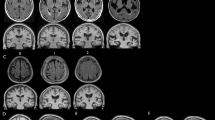

Figure 7 shows representative cases of a young and older adult, which illustrates the group-level observation of PSD volume increasing with age.

Difference of PSD volume between a young adult (top row) and older adult (bottom row). Label maps are produced by the automatic segmentation method. In red, voxels assigned as sinus and contributing veins, in green voxels assigned as PSD space. The two middle columns show the slices extracted on the: (A, C) posterior aspect of the frontal lobe, and (B, D) the anterior aspect of the parietal lobe (i.e., area that shows greatest PSD volume enlargement). On the right, 3D surfaces representation of the brain and its PSD